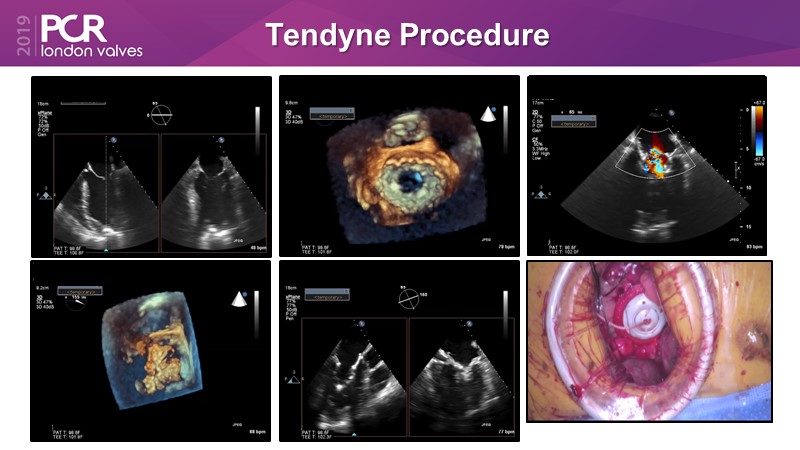

Consult this session on mitral and tricuspid transcatheter valves therapies to learn all about the recent innovations and clinical evidences, and discover the Tendyne Clinical Program, a new transcatheter treatment option that eliminates mitral regurgitation.

- To review the Tendyne Clinical Program and learn of a new therapy in high surgical risk patients in whom good repair results are unlikely